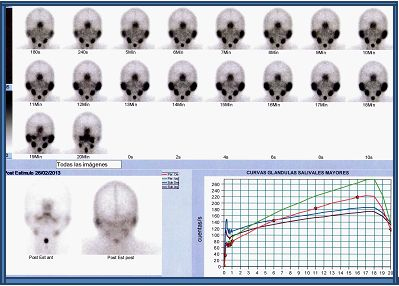

La función salival se estimó mediante la gammagrafía de glándulas salivales con administración endovenosa de 370 MBq (10 mCi) de 99mTc-pertecnetato. Los pacientes estuvieron en ayunas y fueron estudiados en posición decúbito supino, con una gammacámara de dos cabezales (Siemens E.cam, Hoffman Estates, EEUU). La adquisición fue realizada en modo dinámico en proyección AP en matriz 128x128 word a razón de 1 “frame” por minuto durante 60 minutos, incluyendo post estímulo con jugo de limón a los 15 min (21,23). Se construyeron cuatro regiones de interés ovaladas, posicionadas sobre las parótidas y submaxilares y se generaron curvas de actividad en función del tiempo (gráficas roja y verde correspondientes a las parótidas, marrón y verde a las submaxilares (21). Dependiendo de las características de captación y la excreción de las glándulas salivales, los pacientes se clasificaron en uno de cuatro patrones diferentes: Grado I, con captación y excreción normal (Fig. 1); Grado II, disfunción leve a moderada, caracterizada por disminución de la captación salival y retraso en la excreción, siendo la actividad oral igual en intensidad a la captación salival a los 60 min (Fig. 2); Grado III, disfunción moderada a severa, con marcada disminución de la captación de las glándulas salivales, excreción retardada y captación glandular mayor que la actividad oral a los 60 min; Grado IV, disfunción severa con disminución marcada de la captación glandular y la actividad de fondo más alta que la salival durante todo el estudio (22,23).